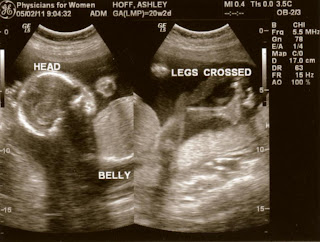

Things went very well. All body parts/organs looked good and measured on track. Baby is measuring at 13 ounces, which puts him in the 65th percentile or so. I'm 20 weeks and 2 days along, and baby is 20 weeks 3 days. My belly measured 21 cm. I'm very happy about this because I sometimes worried about how both of us would measure. In my last pregnancy Ethan and I measured behind. The fact that this baby measures right on track, if not a little bit big, makes me feel much better. There were only 2 issues that arose during the scan(though at this point neither one of them is truly a real issue). First, it appears that I currently have placenta previa, meaning that my placenta is covering my cervix. As my uterus grows and thins out, the placenta could be move upwards. We will be doing another ultrasound in 8 weeks to check this. If it still hasn't moved, we will do another a few weeks later. If by 30 something weeks it's still covering my cervix, I'll have to have a c-section. In the meantime I have to be careful not to do anything strenuous (not a problem!) to avoid causing any bleeding.

Second, there was a small cyst (a choroid plexus cyst) on part of the brain (I believe the part that produces fluid?). The tech told us that sometimes they see this at this point in an ultrasound, and sometimes they don't. Usually this type of cyst disappears on its own by 30 weeks and is not cause for concern. She and the doc agreed that since our first trimester screening was good and everything else with baby looked healthy, it's not anything to worry about at this point. They will also check for that at my 28 week ultrasound. I'm not feeling worried about it at the moment, but I'm curious if anyone else has had experience with this or knows someone whose baby had one of these cysts? (preferably positive experiences!) I looked on Baby Center and all of the posts I read from women said that their babies had one and it either disappeared before birth, or the baby was born with it and it had no affect on it. Keith and I still feel like all is well with baby, but of course we pray that this cyst is gone by the next ultrasound.

This one was actually two shots that the tech pieced together so that we could see the whole body together: